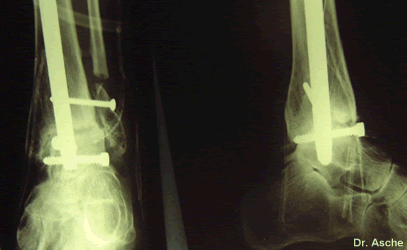

Nach 8 Tagen konnte die Patientin aus dem Krankenhaus entlassen werden. Sie war völlig beschwerdefrei und konnte schon mit Teilbelastung beginnen.

Der Befund 8 Tage nach der Operation.